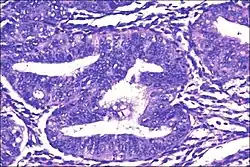

| Micrograph showing simple endometrial hyperplasia, where the gland-to-stroma ratio is preserved but the glands have an irregular shape and/or are dilated. Endometrial biopsy. H&E stain. | |

Endometrial hyperplasia is a condition of excessive proliferation of the cells of the endometrium, or inner lining of the uterus.[1]

Like other hyperplastic disorders, endometrial hyperplasia initially represents a physiological response of endometrial tissue to the growth-promoting actions of estrogen. However, the gland-forming cells of a hyperplastic endometrium may also undergo changes over time which predispose them to cancerous transformation. Several histopathology subtypes of endometrial hyperplasia are recognisable to the pathologist, with different therapeutic and prognostic implications.[4]

- Endometrial hyperplasia (simple or complex) - Irregularity and cystic expansion of glands (simple) or crowding and budding of glands (complex) without worrisome changes in the appearance of individual gland cells. In one study, 1.6% of patients diagnosed with these abnormalities eventually developed endometrial cancer.[7]